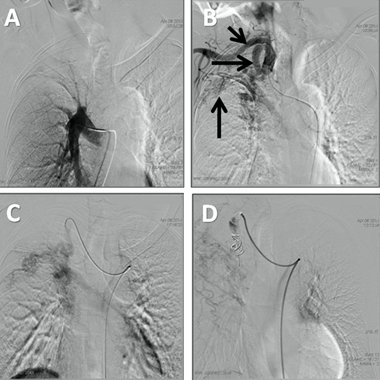

Figure 1: Computed tomography pulmonary angiogram using OmnipaqueTM contrast medium and the smart prep protocol. (A) Coronal multiplaner reconstruction identifying fibrotic changes in the right upper lobe. (B) Lung window axial image showing bronchiectasis and volume loss in the right upper lobe, and some tree-in-bud lung opacities at the right inferior lobe spical degment. (C, D, E) Axial images showing multiple tortuous vascular structures in the right thoracic wall, adjacent to the mammary vessels. It also illustrates prominence of the right internal mammary vessel.

A 47-year-old male presented to our institution with massive hemoptysis in which approximately 150 cm3 of blood was expectorated at least twice a week in a period of 18 months. He had been treated in another institution for pulmonary tuberculosis six years ago. This was after the diagnosis with serial spontaneously sputum stains positive for acid-fast bacilli. He had to repeat this treatment in spite of the following negative smears because of the persistent hemoptysis, which had also increased in volume and frequency. Despite recurrent hemoptysis, the patient was brought to our institution four years after he finished treatment. On examination, he had low weight, and we found a continuous murmur at the level of the right superior thorax. We did not find vascular lesions in his mouth or on his skin. The rest of the physical examination was normal. The laboratory data including complete blood count and blood chemistries were also normal. Pulse oximetry at rest showed normal values. The patient denied any past history of liver disease. Computed tomography (CT) scan of chest revealed signs of volume loss and bronchiectasis involving the right superior lobe. We found an unusual image of vascular characteristic at the level of the right internal mammary artery. There were no caverns or suspicious images of pulmonary arteriovenous malformations (Figure 1). We decided to undertake an angiographic evaluation in which we observed a high flow systemic to pulmonary arteriovenous fistula from the internal mammary and right subclavian arteries, to the right upper lobar veins. We proceeded to perform embolization using two interlock coils and two amplatzer vascular plugs until the internal mammary artery was completely cut-off (Figure 2). The spirometric data showed a FEV1=2820 mL (82% ref), FVC=3050 mL (69% ref), and %FEV1/FVC=92. The patient was discharged after two days of hospital stay with resolution of the hemoptysis. The patient remains asymptomatic for dyspnea and hemoptysis.